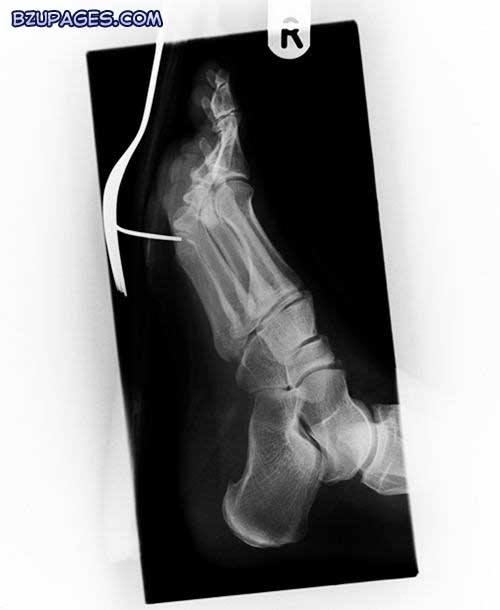

Attachment 21980

A historical X-ray of the foot of a Boer War (1899-1902) soldier, showing a gunshot wound. A Mauser bullet has become lodged between the metatarsal bones of the big and second toes. The bullet has not broken any bones; but the end phalanges of the toes are deformed, perhaps from tight army boots and long marches. This radiograph was made by the soldier positioning his foot above a photographic plate, while an open electric discharge tube emitted the X-rays